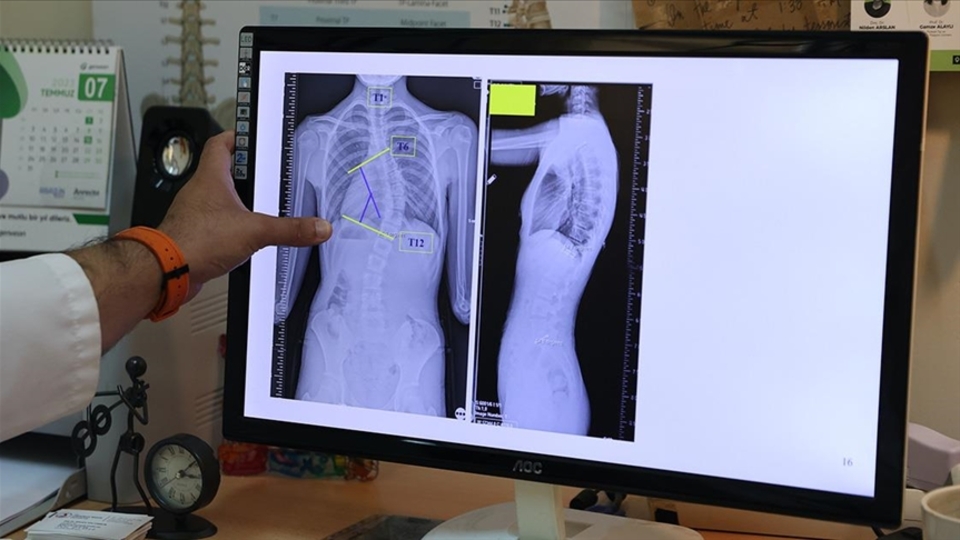

Doç. Dr. Coşkun, omurganın ön ve arka planında 10 dereceden fazla olan eğriliği skolyoz hastalığı olarak kabul ettiklerini belirtti.

Coşkun, skolyozun genellikle 10-19 yaş aralığında görüldüğüne işaret ederek, "Skolyoz, nedeni bilinmeyen bir hastalıktır. Ergenlik, adölesan idiopatik skolyozun en sık görülen yaş grubunu oluşturmakta. Şikayetler genelde omuzların bir tarafında yükseklik farkı olması, bir omuzun daha yukarıda yerleşmesi. Ayrıca hasta öne doğru eğildiğinde, hastada bir tarafında sırtında bir yükseklik, bir kamburluk bulgusu olması. Bu yükseltinin bir tarafta belirginleşme, diğer tarafta silinme, skolyozun ana bulgularındandır" dedi.

Skolyozun tedavisinin mümkün olduğunu ve genellikle kabul görmüş üç tedavi şeklinin olduğunu aktaran Coşkun, şöyle devam etti: "Skolyoz hastalığında tedavilerden biri gözlem tedavisidir. Gözlem skolyozda bir tedavidir. Biz gerçekten de 0 ila 20 derece arasındaki eğriliklere pek bir şey yapmayız. Bu çocukların gelişimini takip ederiz ve erişkin yaşa geldiğinde de bu tedaviyi sonlandırırız. Artık bu çocukların bir riski, hastalığın ilerlemesi açısından yoktur. 20 ila 40 derece arasında ise ya da 45 dereceye kadar biz çocuğun yaşı eğer uygunsa korse tedavisi uygularız. Korse tedavisi için çocuğun büyümesinin devam etmesi lazım. Kemik yaşı tamamlan, büyümesi tamamlanmış bir çocukta korse tedavisinin yeri yoktur. 45 dereceyi aşan eğriliklerde ise eğriliğin her sene ilerleyeceğini öngörerek cerrahi tedavi uygulamaktayız."

Skolyozun özellikle kız çocuklarında daha sık görüldüğünün altını çizen Coşkun, ergenlik öncesi çekilecek bir omurga röntgeninin tedavide daha iyi yol alınmasını sağlayacağına işaret ederek, "Kız çocuklarında doğumsal kalça çıkığında olduğu gibi skolyoz yönünden tedbirli olmakta fayda var. Özellikle adet öncesi dönemde kızların en azından bir omurga röntgeninin çekilmesi, yine erkeklerde de ergenlik öncesi dönemde bir kez omurga röntgeninin çekilmesi olası bir skolyoz hastalığının tedavisine erken başlamak adına önemli. Çünkü tedaviye ne kadar erken başlarsak o kadar iyi sonuç alma ihtimalimiz yüksek" ifadelerini kullandı.